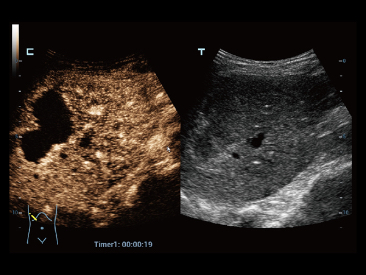

Desde que se fundó la compa?ía, Mindray ha explorado incansablemente nuevas formas de mejorar la confiabilidad del diagnóstico. Con la revolucionaria tecnología de ZONE Sonography?, la nueva plataforma ZST+ de Resona?7 lleva la calidad de la imagen por ecografía a un nivel superior mediante el procesamiento de datos de canal y la adquisición de zona.

Además de la calidad de imagen de primer nivel, Resona?7 también mejora las capacidades de investigación clínica con el revolucionario V?Flow para la evaluación hemodinámica vascular y con la adquisición de planos más inteligente a partir de conjuntos de datos 3D para el diagnóstico del SNC fetal. Al combinar el funcionamiento multitáctil basado en gestos más intuitivo y todas las características clínicas esenciales, Resona?7 realmente lidera las novedades en innovación de ecografías.